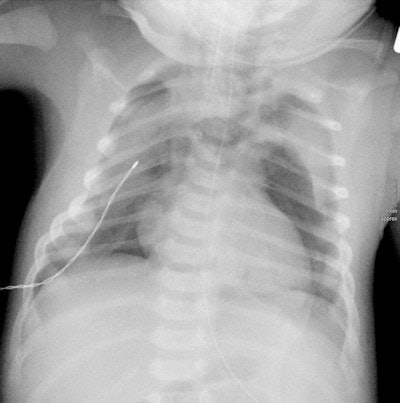

A real clinical feel for the work, coupled with a "radiological eye." Pediatric radiologists need a thorough knowledge of childhood disorders because these differ widely from their adult counterparts. Furthermore, when dealing with children it is a fundamental necessity that practitioners give greater thought to radiation doses, because children are far more sensitive to radiation than adult patients are. Their tissue is still growing and there are also matters of reproduction to consider, so a particularly close watch needs to be kept, to ensure that the smallest possible amounts of radiation are used. This means using caution and having a reliable indication before opting for x-ray and CT scanning for investigations.

The upshot of this is that, as a pediatric radiologist, one must have a particularly sound knowledge of MRI and ultrasound techniques. Research in these fields is therefore also of particular importance for pediatric radiologists.

In March, our focus will be upon conventional x-ray investigations during childhood. Assessing pediatric x-rays is one of the most difficult tasks, calling for a great deal of clinical and radiological experience. From my lengthy experience as a pediatric radiologist, I can tell that a lot of colleagues, radiologists, and clinicians who have not had appropriate training find it difficult to reach the correct diagnosis or to come up with normal findings. There are, in fact, major differences between children and adults. A finding that is normal in a child can be pathological in an adult, even a suspected tumor. Furthermore, children are not little adults.